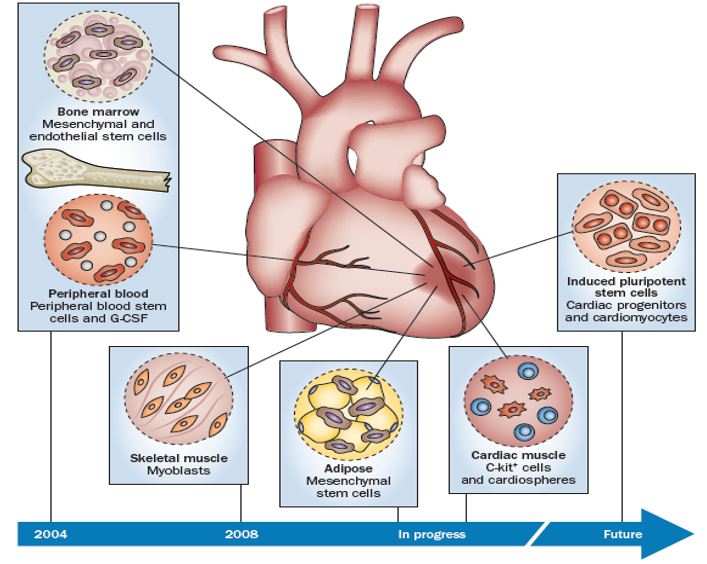

Revolutionary Stem Cell Therapy Offers New Hope For Heart Failure Patients

IJMS Free Full Text Cardiac Stem Cell Loaded Delivery Systems A